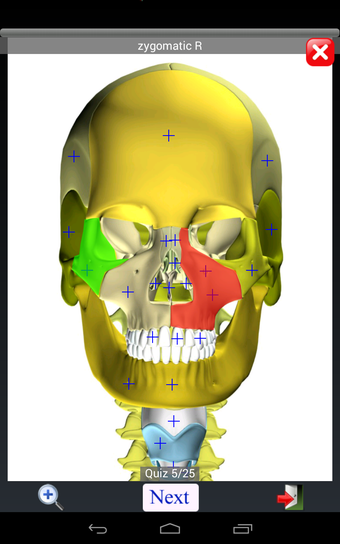

Anatomy Quiz Free es una aplicación de Android de Education Mobile que ofrece una amplia gama de cuestionarios para ayudar a los usuarios a aprender anatomía humana. La aplicación cuenta con más de 500 cuestionarios que ponen a prueba tu capacidad para identificar la ubicación correcta de un objeto dado su nombre. Los cuestionarios se generan a partir de modelos de anatomía 3D virtuales, lo que los hace más atractivos e interactivos. La aplicación es gratuita y no hay versiones premium ni compras dentro de la aplicación.

La aplicación es compatible con los idiomas inglés, francés, español y alemán, lo que la hace accesible para usuarios de diferentes partes del mundo. Las imágenes de alta resolución son nítidas y claras, y la función de zoom con pellizco te permite acercar y alejar las imágenes para una mejor vista. El cuestionario de posición viene con un temporizador, lo que lo hace más desafiante y emocionante. Además, la aplicación tiene una función de transferencia a la tarjeta SD, lo que facilita su transferencia a otros dispositivos.